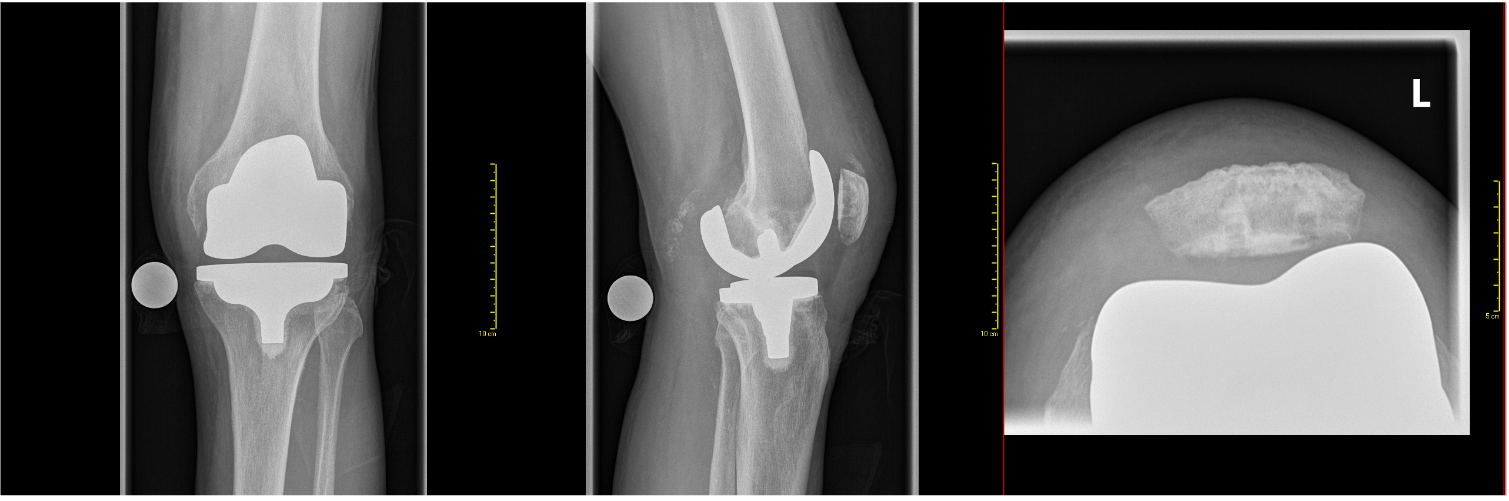

Beispiel eines Planungsreportes für das «kinematic Alignement» nach CT graphischer Vermessung für die operative Versorgung mit den PSI und postoperative Röntgenkontrolle (Orthoradiogramm und Knie links a.p.-seitlich mit Patella tangential) Aufnahme bei Patellarückflächenersatz